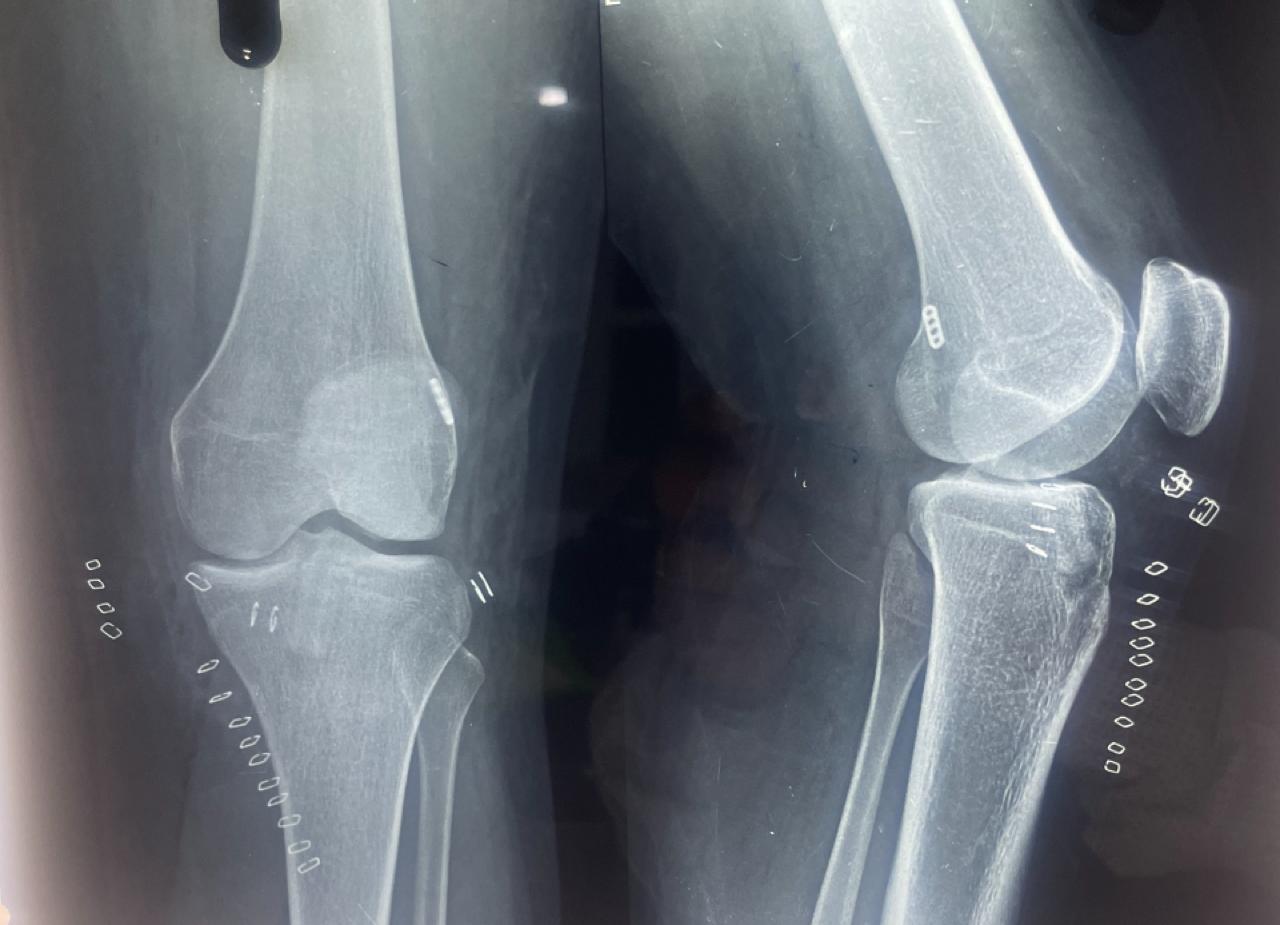

Images of ACL Surgery:

ACL Surgery